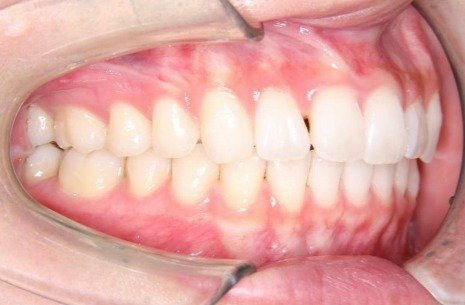

掲載症例について:

患者】 10代女性

【主訴】 前歯のガタガタ

【診断】 過蓋咬合を伴う叢生

【抜歯の有無】 非抜歯

【治療期間】1年8ヶ月 通院回数12回

【治療内容】親知らずを抜歯した後、マウスピース型カスタムメイド矯正歯科装置(製品名インビザライン 完成物薬機法対象外)を使用して主訴である叢生および過蓋咬合の改善を行いました。

【費用】88万(税込)

【リスク】矯正歯科装置を付けた後しばらくは違和感、不快感、痛みなどが生じることがあります。

矯正中は矯正歯科装置が歯の表面についているため食物が溜まりやすく、また歯が磨きにくくなるため、虫歯や歯周病が生じるリスクがあります。

歯を動かすことにより歯根が吸収して短くなることや歯肉がやせて下がることがあります。

矯正歯科治療は公的健康保健の適応外の自費治療(自由診療)となります。